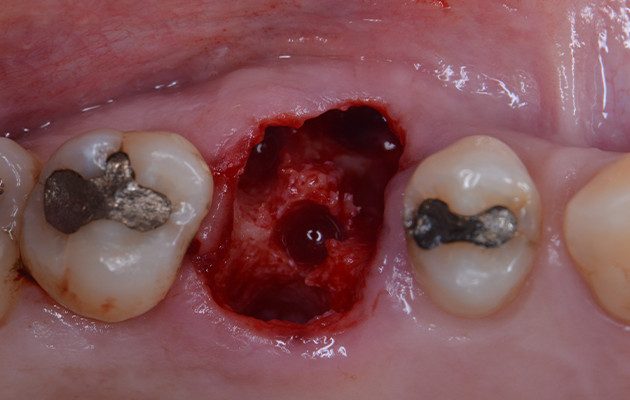

6 | Aspecto do leito cirúrgico após protocolo de fresagem.

7 | Implante dentário pronto para inserção.